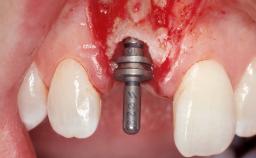

Immediate Flapless Placement of an Implant in a Maxillary Right Lateral Incisor Site

This 43-year-old male patient, a non-smoker, came to our practice because of a fracture of tooth 12 caused by a bicycle accident. Due to the combined para- and infrabony crown and root fracture, tooth extraction, and subsequent implant placement were suggested to the patient as the therapy of choice. The patient had high esthetic expectations with regard to the treatment outcome and asked for an immediate fixed provisional restoration. His individual esthetic risk profile summed up to a medium esthetic risk.

Type of Implants Two-Piece

Loading Protocol Immediate

Retention Screw-retained Screw-retained

Provisional Implant-Supported Prosthesis Prosthodontic margin > 3 mm apical to mucosal margin Prosthodontic margin > 3 mm apical to mucosal margin